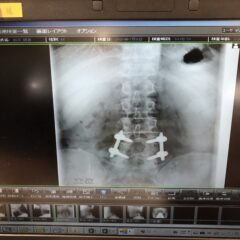

57年生きてきて色んなことがあったなぁとつくづく思う。 その度に気付かされる。 いや、気づかないから気付かされる方向に持って行かれるのだと。 体を傷みつけて、傷つけて、体に対して敬う気持ちが全く...